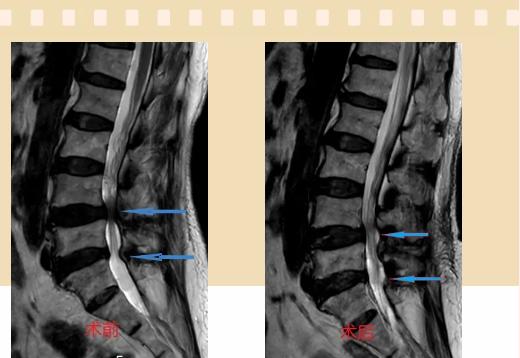

入院后李鵬副主任醫(yī)師為其進(jìn)行了詳細(xì)的查體,完善了術(shù)前的檢查,明確診斷為:腰椎管狹窄癥(L4/5、L5/S1),病人合并2型糖尿病,請(qǐng)內(nèi)分泌科會(huì)診,穩(wěn)定血糖后,麻醉科會(huì)診病人,排除手術(shù)禁忌,李鵬為病人制定了手術(shù)方案:?jiǎn)蝹?cè)入路雙側(cè)減壓(ULBD)。

手術(shù)采用三個(gè)微創(chuàng)小切口,兩個(gè)節(jié)段減壓手術(shù)時(shí)間2.5小時(shí),出血50ml。術(shù)后2天腰圍保護(hù)下床活動(dòng),術(shù)后5天順利出院。

傳統(tǒng)腰椎管狹窄癥的手術(shù)治療,往往需要切開(kāi)減壓,同時(shí)需要內(nèi)固定融合術(shù),創(chuàng)傷很大,同時(shí)可能需要輸血,臥床時(shí)間較長(zhǎng),病人合并糖尿病,感染風(fēng)險(xiǎn)也高,而本次采用的UBE-ULBD手術(shù)切口更小(加起來(lái)約3cm,如果是單節(jié)段狹窄只需要不到2cm切口)、創(chuàng)傷更小,術(shù)后恢復(fù)較快,可以更早地恢復(fù)正?;顒?dòng)。

此外,手術(shù)保留了病變節(jié)段的穩(wěn)定性,是一種微創(chuàng)的椎管減壓手術(shù),能通過(guò)切除部分椎板、關(guān)節(jié)突關(guān)節(jié)、黃韌帶來(lái)解除神經(jīng)根和硬膜囊的壓迫,不需要額外行腰椎內(nèi)固定術(shù),不需要螺釘及融合器的植入,病人術(shù)后腰椎的活動(dòng)度不受影響。(盧   闖  劉   旭   袁錦鈺)